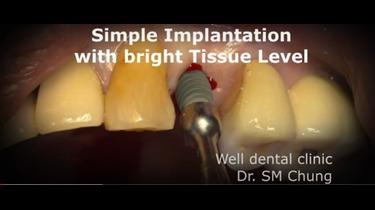

Simple Implantation with bright Tissue Level